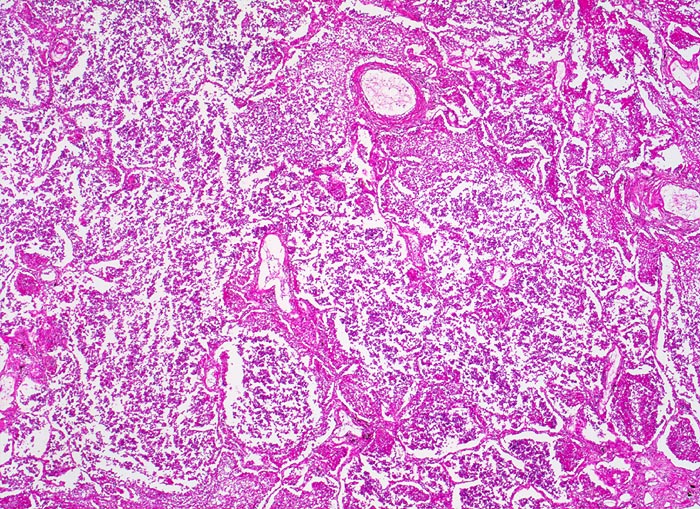

Aufgrund der heute rasch einsetzenden antibiotischen Therapie bei klinischer Diagnose einer Pneumonie, kommen die charakteristischen Stadien der Lobärpneumonie nur noch selten zur Beobachtung. Die unbehandelte Lobärpneumonie verläuft in vier Stadien:

Anschoppung (1. -2. Tag)

Rote Hepatisation (2.-3. Tag)

Graue Hepatisation (4.-6. Tag)

Gelbe Hepatisation (7.-8. Tag)